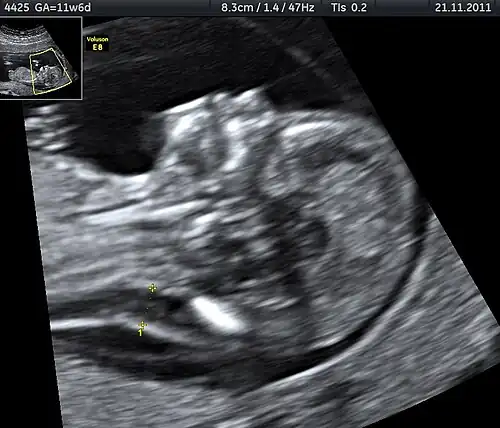

| Ultrasound is often used to diagnose stillbirth and medical conditions that raise the risk. | |

Often the cause is unknown.[1][12] Causes may include pregnancy complications such as pre-eclampsia and birth complications, problems with the placenta or umbilical cord, birth defects, infections such as malaria and syphilis, and poor health in the mother.[2]: Causes tab, [3][13] Risk factors include a mother's age over 35, smoking, drug use, use of assisted reproductive technology, and first pregnancy.[4] Stillbirth may be suspected when no fetal movement is felt.[5] Confirmation is by ultrasound.[5]

It is unknown how much time is needed for a fetus to die. Fetal behavior is consistent and a change in the fetus' movements or sleep-wake cycles can indicate fetal distress.[30] A decrease or cessation in sensations of fetal activity may be an indication of fetal distress or death,[31][32] Still, medical examination, including a nonstress test, is recommended in the event of any type of any change in the strength or frequency of fetal movement, especially a complete cease; most midwives and obstetricians recommend the use of a kick chart to assist in detecting any changes.[33] Fetal distress or death can be confirmed or ruled out via fetoscopy/doptone, ultrasound, and/or electronic fetal monitoring.[34] If the fetus is alive but inactive, extra attention will be given to the placenta and umbilical cord during ultrasound examination to ensure that there is no compromise of oxygen and nutrient delivery.[35]